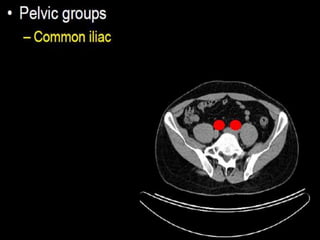

CT cross sectional anatomy.